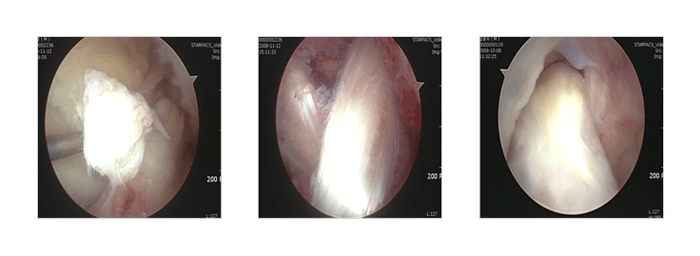

전방 및 후방십자인대 파열

무릎 내에는 위뼈와 아래뼈를 연결하여 앞,뒤로 흔들리는 것을 막아주는 인대가 있는데 서로 십자 모양으로 cross 하고 있어 각각 전방, 후방 십자인대라 부릅니다. 이 인대들 역시 운동 중 수상이나 교통사고, 산업 재해로 많이 파열되는데 끊어진 채 오래 방치 하면 무릎의 불안정성을 초래하여 통증, 부종, 어긋나는 증상을 초래하게 되고 더 나아가 연골판 손상, 관절연골 손상을 일으켜 관절염으로 진행하게 됩니다. 이때 수술은 관절 내시경을 이용하여 봉합이나 재건술을 합니다. 물론 모든 경우에 수술이 이용되는 것은 아니고 경도의 부분 손상은 보존요법을 통해 근력 강화를 시키면서 치료할 수도 있고 간단한 shrinkage ( 수축술 ) 만 시행하는 경우도 있으니 전문의의 정확한 진찰과 판단 그리고 환자와의 상의가 더욱 중요한 손상입니다

전방 및 후방십자인대 파열 - 사진